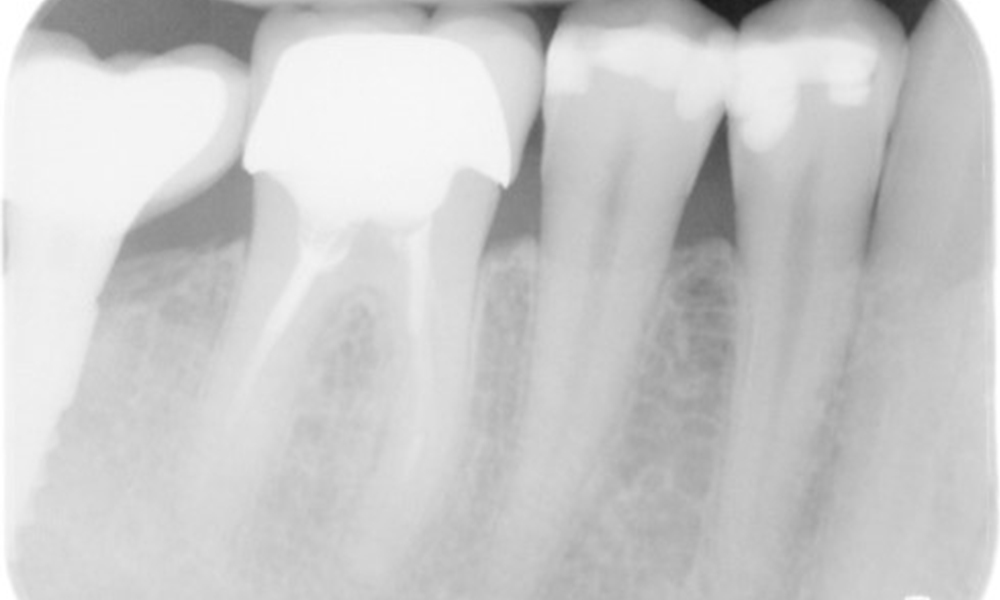

The X-ray image shows the bone loss

The X-ray images show the bone loss.

X-ray images (or bitewing X-rays)

X-ray images (or bitewing X-rays) taken on: 18/02/2021